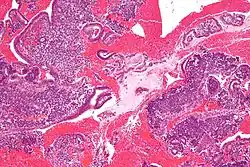

Small blue round cells of Ewing Sarcoma

In histopathology, a small-blue-round-cell tumour (abbreviated SBRCT), also known as a small-round-blue-cell tumor (SRBCT) or a small-round-cell tumour (SRCT), is any one of a group of malignant neoplasms that have a characteristic appearance under the microscope, i.e. consisting of small round cells that stain blue on routine H&E stained sections.

These tumors are seen more often in children than in adults. They typically represent undifferentiated cells. The predominance of blue staining is because the cells consist predominantly of nucleus, thus they have scant cytoplasm.[1][2]